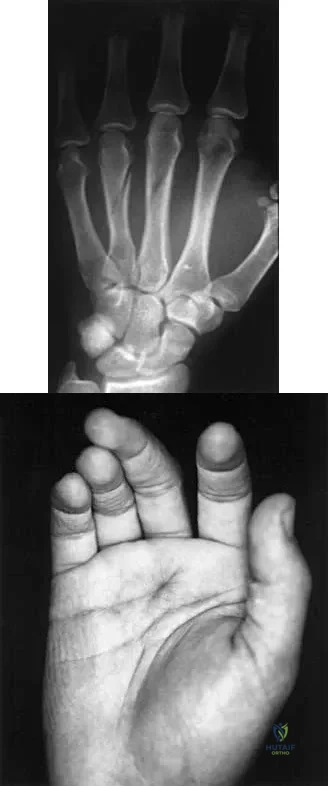

A 23-year-old woman sustains an injury to her right hand after falling off her snowboard. Examination reveals that she has difficulty moving her fingers. A radiograph and a clinical photograph are shown in Figures 8a and Figure 8b. Management should consist of

The radiograph reveals oblique fractures of the third and fourth metacarpals. The rotational component of the fracture displacement is well visualized on the clinical photograph, which shows scissoring of the middle finger over the ring finger. The fracture obliquity results in rotational deformity that cannot be adequately maintained and held by closed treatment. The treatment of choice is open reduction and internal fixation. Stern PJ: Fractures of the metacarpals and phalanges, in Green DP, Hotchkiss RN, Pederson WC (eds): Green's Operative Hand Surgery, ed 4. Philadelphia, PA, 1999, pp 711-771. Freeland AE, Benoist LA, Melancon KP: Parallel miniature screw fixation of spiral and long oblique hand phalangeal fractures. Orthopedics 1994;17:199-200.